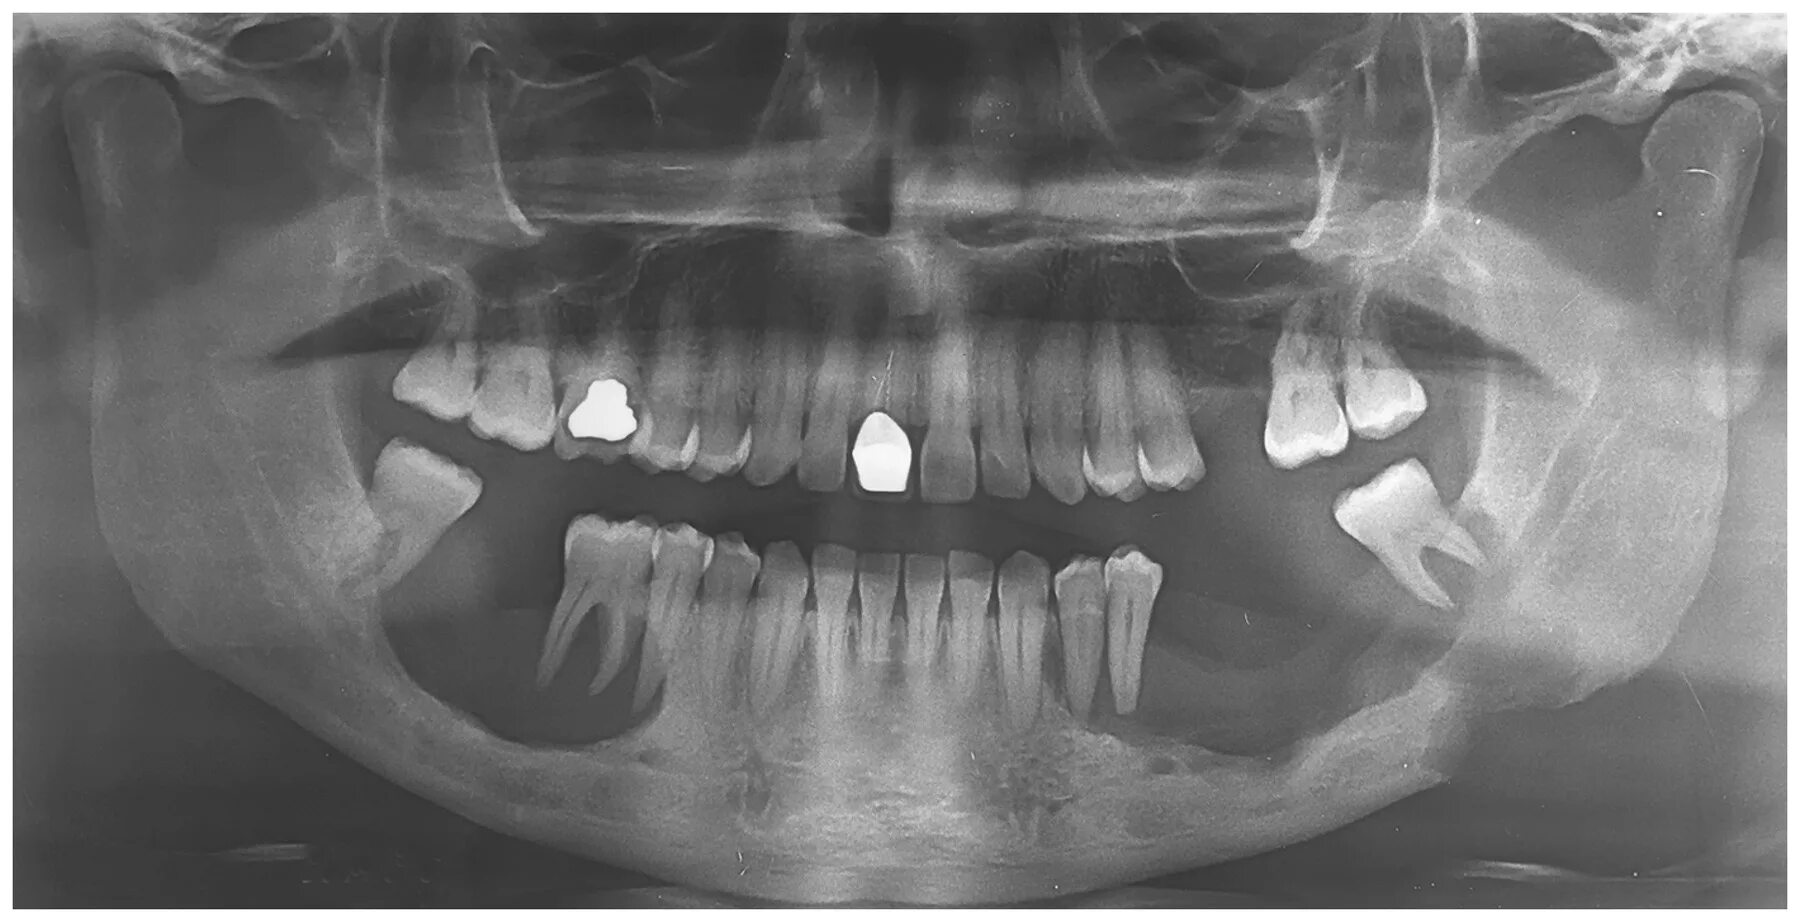

Снимок ротовой полости